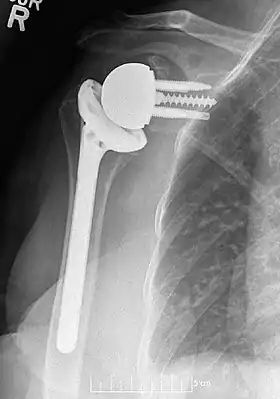

![]() Plain film radiograph in anteroposterior (AP) view of a right shoulder status post reverse shoulder arthroplasty using a prosthesis with a lateralized center of rotation. | |